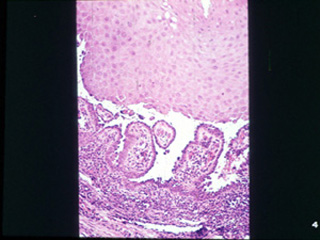

| A mayor resolución se puede observar lo antes dicho;

las ampollas o vesículas son suprabasal. |

A una

mayor resolución las células de la capa de Malpighi sufren un doble

proceso, acantolítico (ruptura de los puentes intercelulares) y

degenerativo. |